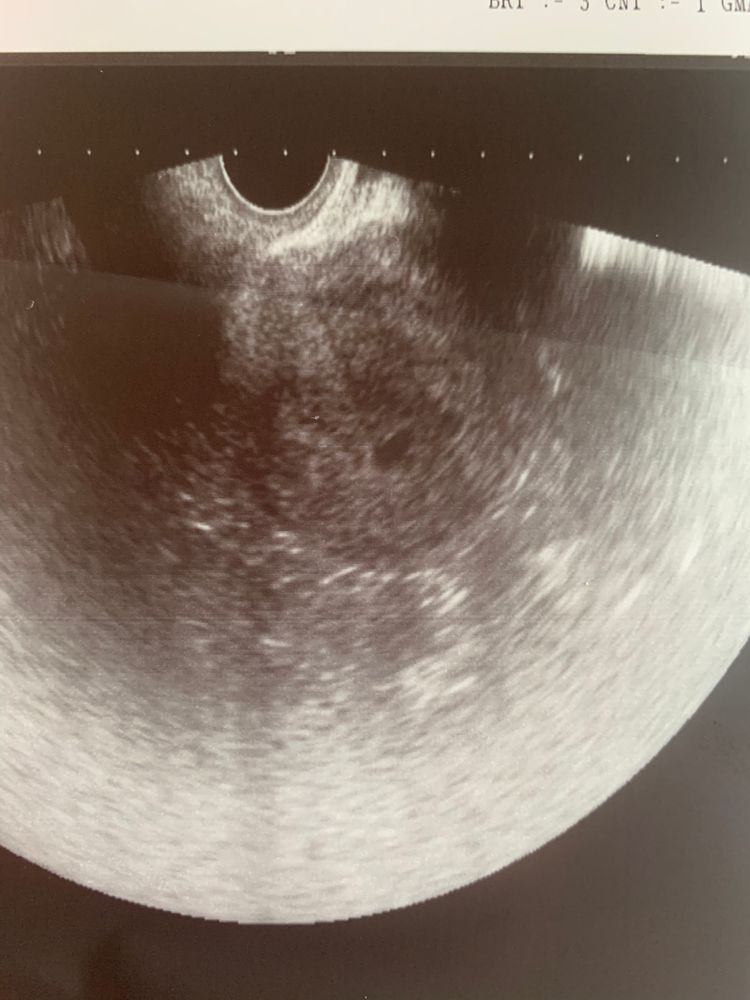

Первое УЗИ -первые эмоции 🙏18 дпп